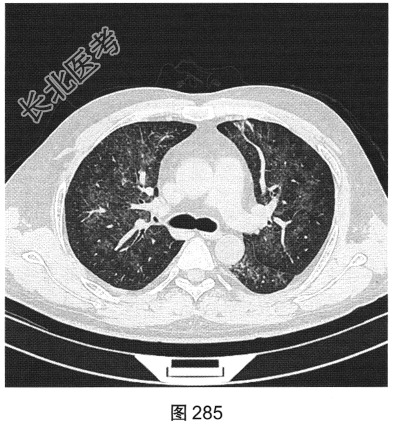

- [材料题] 患者男性,33岁,因“双下肢散在皮下出血点伴尿检异常3个月余,咳嗽、胸闷伴发热一周”就诊。患者脂肪肝、胆囊炎,服用莲葡双清片;随后几日内食用淡水鱼、鱿鱼、饮啤酒;5天后出现双下肢散在皮下出血点,未重视;10天后出现腹痛,在当地医院检查尿中有蛋白、定量不详,血常规检查正常,肾功能正常,应用醋酸泼尼松效果欠佳,行肾活检术,病理诊断:紫癜性肾炎,继发IgA肾病。患者每天静脉滴注甲泼尼龙0.5g,共3天,后改为口服甲泼尼龙28mg/d,共35天。一周前着凉后出现咳嗽、胸闷伴发热,体温达39.1℃,于当地医院抗炎治疗效果欠佳,遂来本院。实验室检查:血白细胞计数6.92×109/L,中性粒细胞0.845,CRP为2.7mg/dl。患者PP65阳性。胸部CT检查如图284~图287所示。

- 多项选择题1.患者的主要影像特征是( )

A、双下肺为著

B、伴细网格影

C、血管支气管束增厚

D、小叶中央结节

E、以磨玻璃密度为主

F、双肺弥漫分布